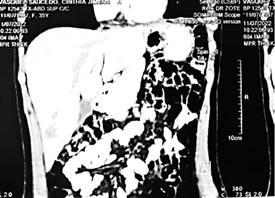

• Paciente en decúbito lateral derecha bajo anestesia general. Toracotomía lateral, se evidencia gran proceso adherencial liberación de sinequias con maniobras romas (FIGURA 3-A). Se identifica adherencia gastropulmonar firme, liberación de la misma pero durante proceso se produce perforación accidental de fondo gástrico reparación mediante sutura en 2 planos con vicryl 3-0 surget continuo primera hilera y la segunda Lembert.

• Por excesiva fibrosis, falta de plano de clivaje y lasitud de diafragma, se procede a plicacion con prolene 1 puntos simples (FIGURA 3-B), instalación de malla de polipropileno y tubos de pleurostomia izquierdos (FIGURA 3-C). Fin de procedimiento sin complicaciones, paciente pasa a UTI (FIGURA 3-D)

FUENTE: PROPIA

FIGURA 3: Hallazgos intraoperatorios

Se realizó TAC de control a 2 meses con evidencia de rectificación de cúpulas diafragmáticas (FIGURA 5) y seguimiento por 6 meses sin intercurrencias.

FUENTE: PROPIA EXPEDIENTE CLINICO

FIGURA 5: TAC contrastada de control